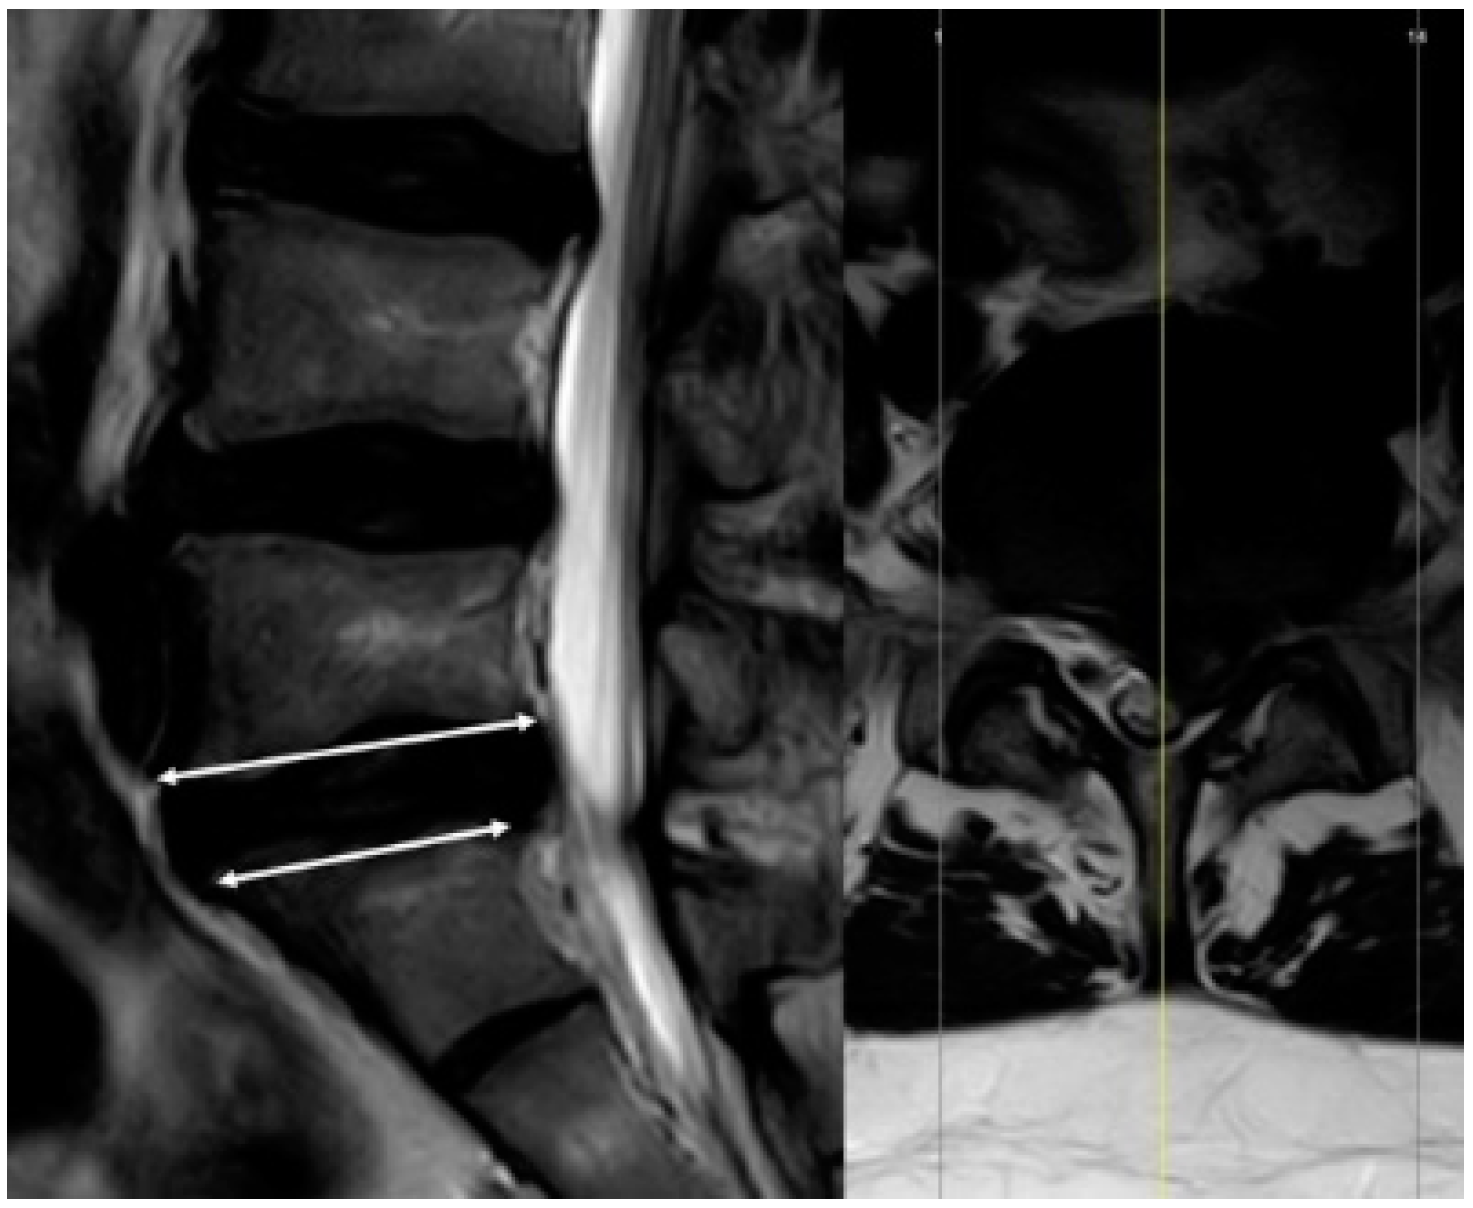

2.6. Measurement

2.7. Theory/Calculations